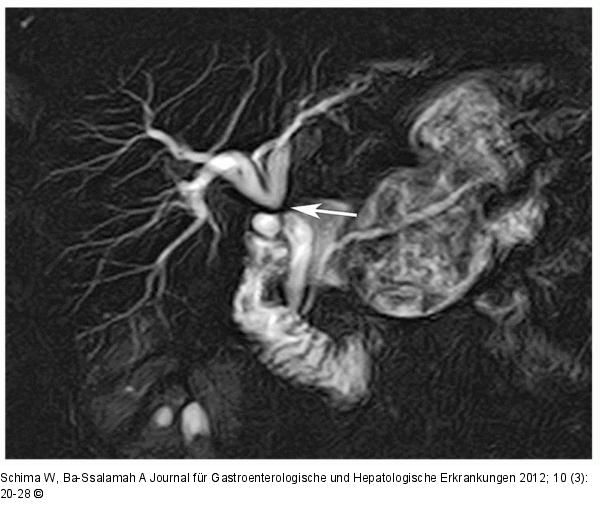

Abbildung 5: Cholecystektomie - Choledochusrevision Striktur nach Cholecystektomie und Choledochusrevision. Die MRCP zeigt eine glatt begrenzte, blendenförmige hochgradige Striktur des Ductus hepaticus communis (Pfeil) mit deutlicher Dilatation der vorgeschalteten Gallenwege. |

Striktur nach Cholecystektomie und Choledochusrevision. Die MRCP zeigt eine glatt begrenzte, blendenförmige hochgradige Striktur des Ductus hepaticus communis (Pfeil) mit deutlicher Dilatation der vorgeschalteten Gallenwege. |